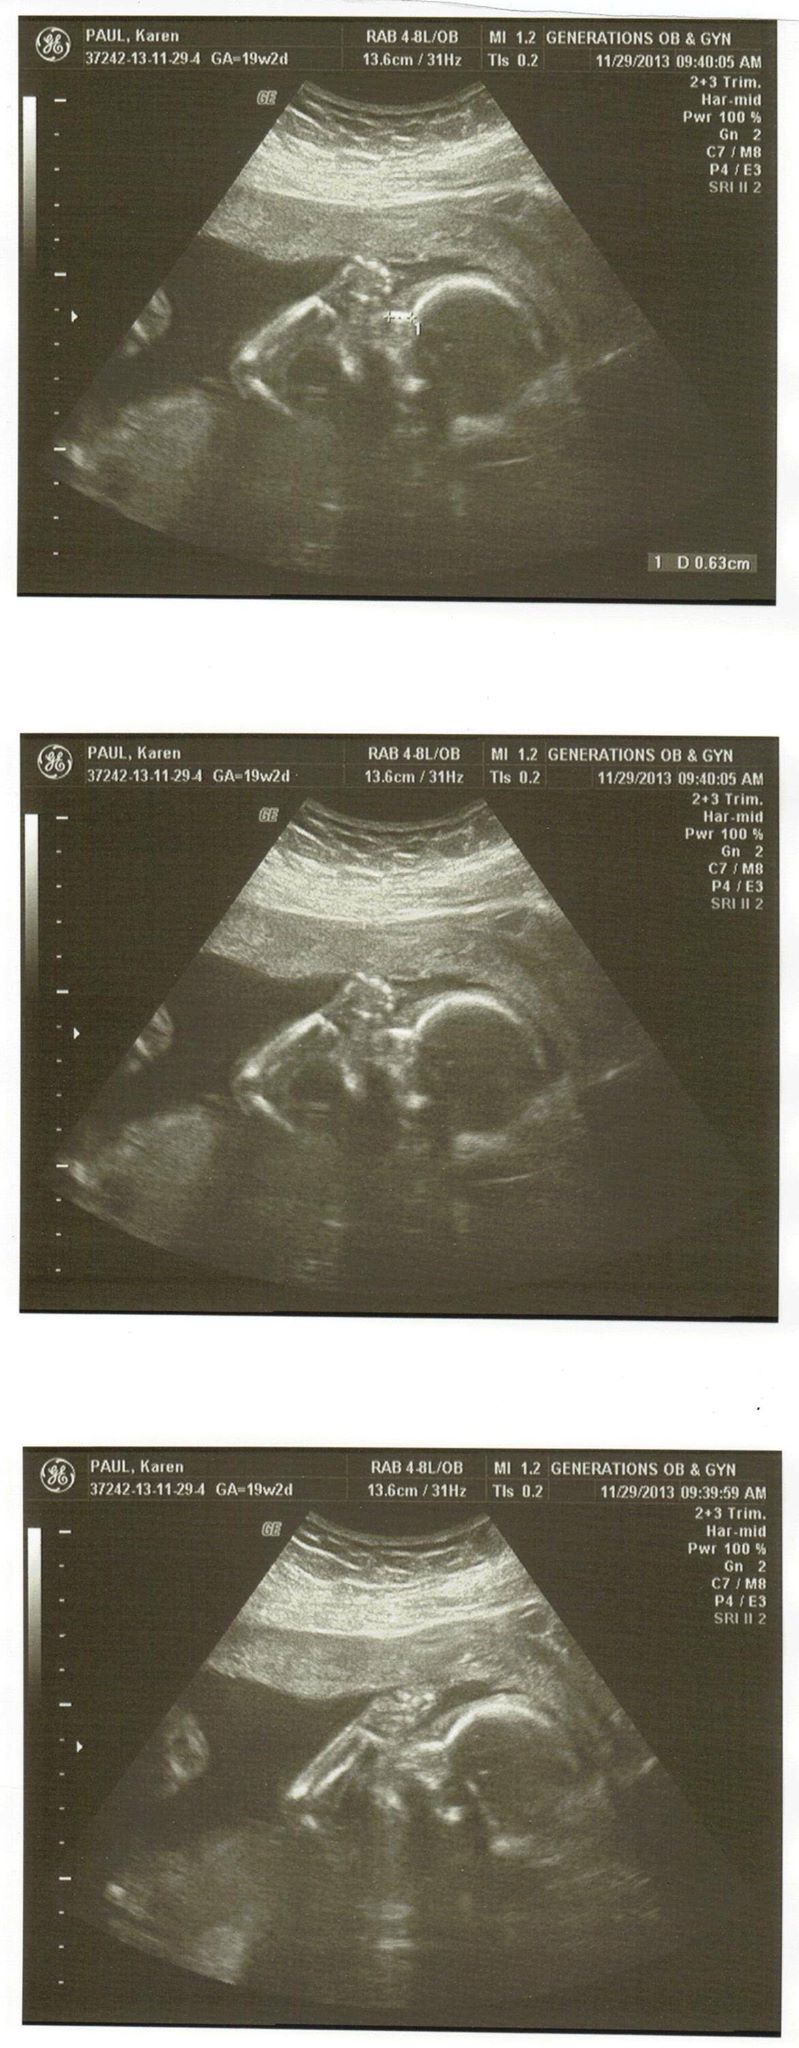

Pregnancy

Pregnancy Photos